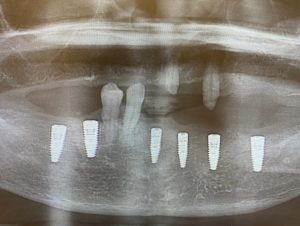

術後パノラマレントゲン

サージカルガイトを用いたため術前シュミレーションと術後レントゲンを比較すると埋入角度、位置がほぼ一致しています。